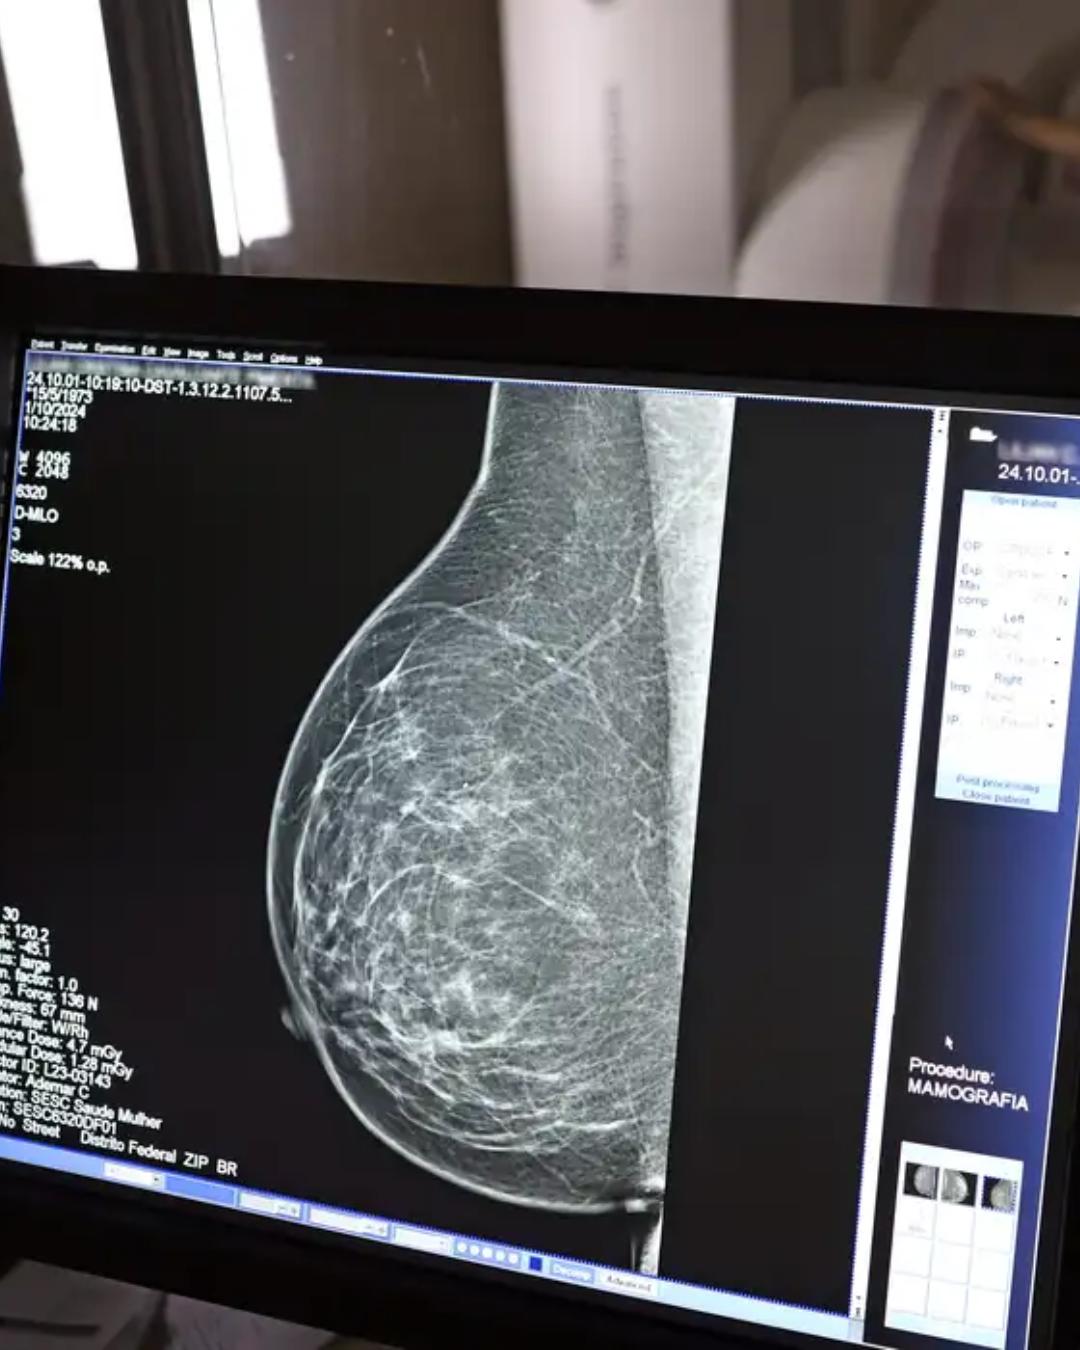

Atualmente, a taxa de cobertura de mamografias é de apenas 24% no Brasil, muito abaixo do índice de 70% recomendado pela Organização Mundial da Saúde (OMS). Mesmo em estados como São Paulo, que concentra a maior quantidade de aparelhos do país, a taxa de cobertura é de apenas 26%. Em uma tentativa de ampliar o rastreamento, o Ministério da Saúde anunciou em setembro novas diretrizes, recomendando mamografias para mulheres entre 40 e 49 anos, mesmo sem sintomas da doença.

O Instituto Nacional do Câncer (Inca) aponta que mais de 73 mil mulheres são diagnosticadas com câncer de mama anualmente no Brasil. Ivie Braga de Paula reforça a eficácia do diagnóstico precoce por meio de exames de imagem. “O que é efetivo na redução da mortalidade é você descobrir o tumor antes de ter sintoma clínico. Quanto menor o tumor, melhor para a gente descobrir o tratamento e maior a chance de cura. E a gente só consegue fazer isso com exames de imagem”, explica. Segundo ela, no caso de tumores com menos de 1 cm, principalmente detectados pela mamografia, a chance de cura pode chegar a 95% em cinco anos, mesmo em casos de câncer mais agressivos. “Essas pessoas que têm que ir fazer mamografia são mulheres saudáveis. Não são mulheres doentes”, conclui Ivie.